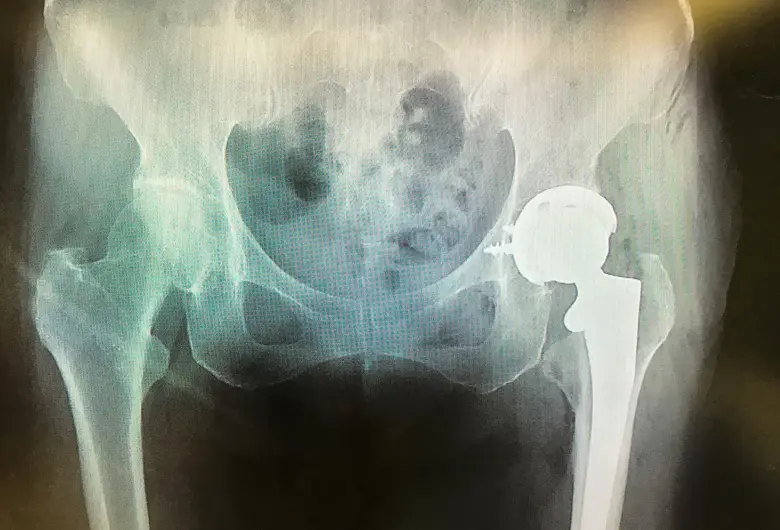

手術 人工股関節置換術(THA)

1: 人工股関節置換術(THA)

3: 手術方法と使用する人工関節

関節軟骨が傷んだ部分を切除し、人工関節を正しい位置に設置します。

使用する人工関節は骨セメントを使用せずにインプラントを骨に直接固定するセメントレス固定型を標準としています。

素材は骨との生体適合性が高いものを採用しています。